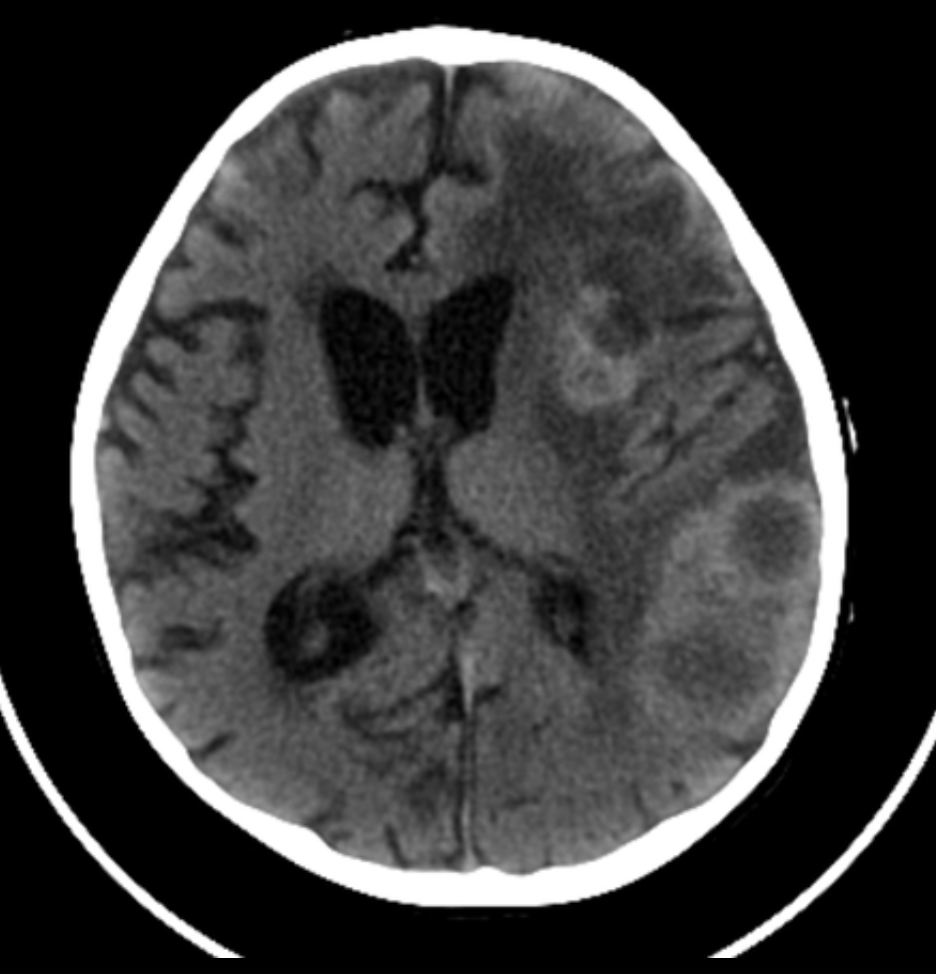

Note the multiple sites of oedema and haemorrhage, involving the brain stem and corpus callosum as well as subcortical white matter and left cerebral peduncle. High FLAIR signal is also seen in the dorsal midbrain. EVD insitu.

Case Discussion

Diffuse axonal injury can be subtle on CT but have devastating consequences for the patient. This is a case of grade III injury (involvement of brainstem) and carries a poor prognosis.

Diffuse axonal injury (DAI), also known as traumatic axonal injury (TAI), is a severe form of traumatic brain injury due to shearing forces. It is a potentially difficult diagnosis to make on imaging alone, especially on CT as the finding can be subtle, however, it has the potential to result in severe neurological impairment.

The diagnosis is best made on MRI where it is characterised by several small regions of susceptibility artifact at the grey-white matter junction, in the corpus callosum, and in more severe cases in the brainstem, surrounded by FLAIR hyperintensity.

CT

Non-contrast CT of the brain is routine in patients presenting with head injuries. Unfortunately, it is not sensitive to subtle diffuse axonal injury and as such, some patients with relatively normal CT scans may have significant unexplained neurological deficit 4,5.

The appearance depends on whether or not the lesions are overtly haemorrhagic. Haemorrhagic lesions will be hyperdense and range in size from a few millimetres to a few centimetres in diameter. Non-haemorrhagic lesions are hypodense. They typically become more evident over the first few days as oedema develops around them. They may be associated with significant and disproportionate cerebral swelling.

CT is particularly insensitive to non-haemorrhagic lesions (as defined by CT) only able to detect 19% of such lesions, compared to 92% using T2 weighted imaging 4. When lesions are haemorrhagic, and especially when they are large, then CT is quite sensitive. As such, it is usually a safe assumption that if a couple of small haemorrhagic lesions are visible on CT, the degree of damage is much greater.